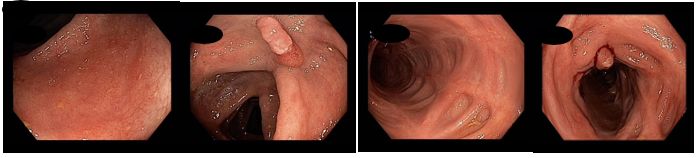

Během pobytu byla pacientka uvedena do klinické remise exklusivní enterální výživou při pokračováním podávání metronidazolu a systémové kortikoterapie s plánem nasazení standardní anti TNF léčby infliximabem nebo adalimumabem po vyřešení administrativních problémů. Během pobytu byla provedena koloskopie s obrazem těžké, segmentální pankolitidy. Z důvodu kolonického postižení podáván mesalazin (v dávce 3,2g/d) a p.o. substituce železem.

Koloskopie 2013/7: Endoskopický obraz těžké, segmentální pankolitidy. Plazivé ulcerace rekta, sigmoidea a descendens. Drobné afty c. transversum a céka. Normální nález v terminálním ileu

Koloskopie 2014: Endoskopický obraz mírné segmentální pankolitidy (aftózní léze, nálety fibrinu, reziduální drobné ulcerace po původně serpiginózních vředech). Nápadné pozánětlivé změny (jizvy, polypy), retrakce zejména v levém tračníku. Normální terminální ileum

Koloskopie 2017/2: Aktivní zánětlivé změny (serpiginózní ulcerace) v oblasti rektosigmatu, mírné zánětlivé změny v blízkosti hepatálního ohbí, segmentálně pozánětlivé změny zejména v levém tračníku (jizvy, retrakce). Normální terminální ileum

Koloskopie 2018/8: Mírné floridní zánětlivé změny (ložiskové zarudnutí a setřelá podslizniční cévní kresba, aftoidní léze) v blízkosti hepatálního ohbí v colon ascendens a v sigmatu. Pozánětlivé změny (jizvy po serpiginózních ulcerací v příčném a levém tračníku, vlevo i pozánětlivá trabekulizace. Normální terminální ileum.

Koloskopie 2022/2: Pozánětlivé změny celého tračníku (jizvy), v rektosigmatu je reziduální ulcerace v centru serpiginózní ulcerace – bez makroskopických známek aktivity v tračníku i terminálním ileu. Vyšetření v bílém světle i NBI